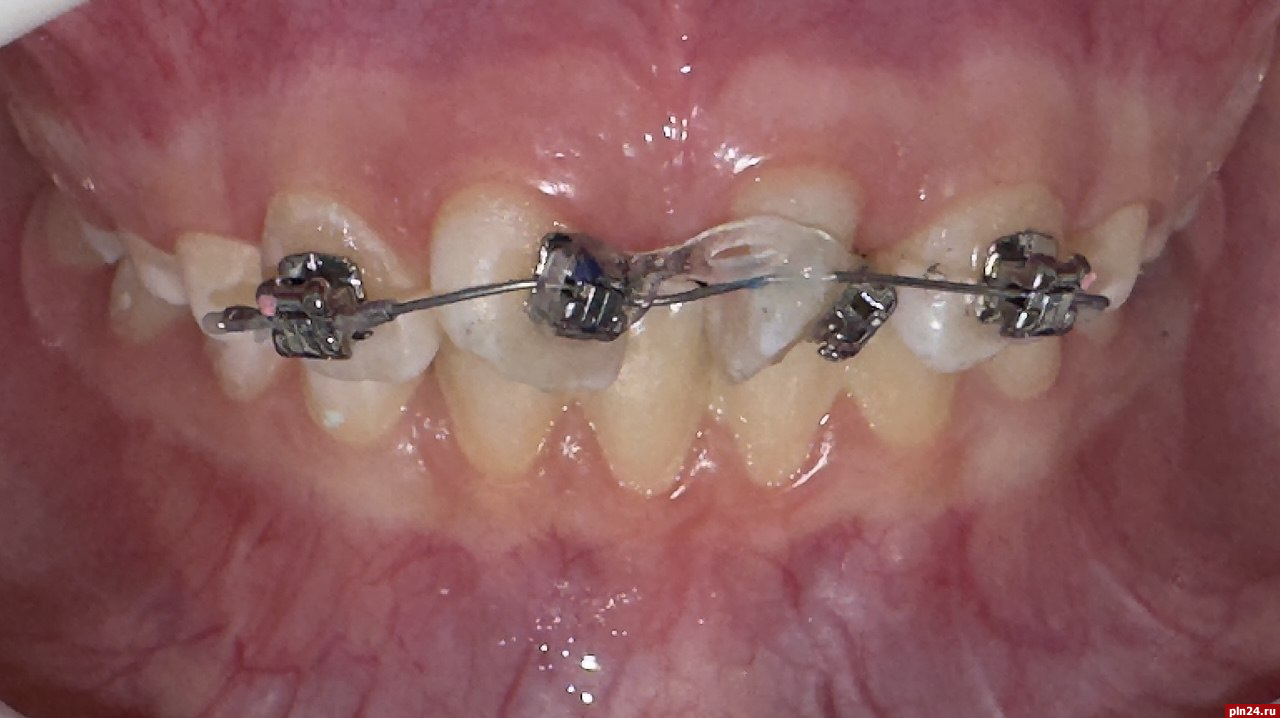

Часто активные пациенты испытывают трудности при ношении съемной аппаратуры (ортодонтических пластинок). Большие конструкции в полости рта вызывают дискомфорт, формируют комплексы у детей, связанные с изменением речи. Ортодонтическая пластинка требует строго режима ношения, что сложно выполнить в период школьного времени.

При остром дефиците места в постоянном прикусе часто прибегают к удалению отдельных зубов. Использование частичной брекет-системы в сменном прикусе позволяет этого избежать.

Частичная брекет-система позволяет решить небольшие ортодонтические проблемы за короткий срок. Пациент испытывает меньший дискомфорт во время лечения, что позволяет добиться хорошего результата.